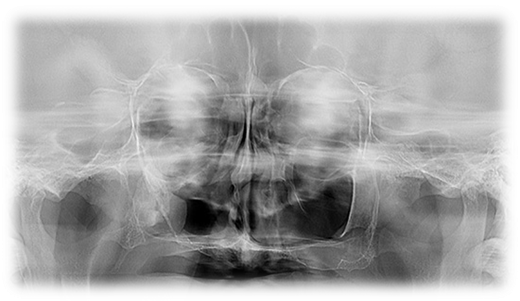

Descriere

Oferă o imagine de ansamblu a oaselor viscerocraniene și parțial a celor craniene, ajutând la stabilirea diagnosticului în ortodonție și chirurgia maxilo-facială.

Imaginea evidențiază și evoluția osificării vertebrelor cervicale, ceea ce permite medicului specialist stabilirea evoluției pre- și post-pubertare a pacientului.